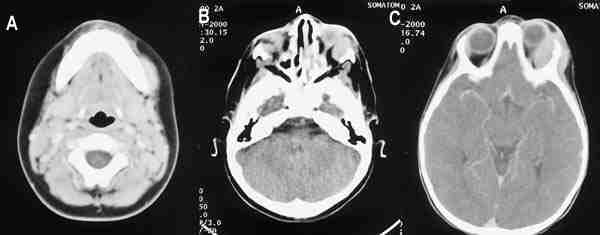

Las leucemias tambien pueden afectar a la órbita siendo los cloromas una de las causas de exoftalmos (figura 8).

53-08.jpg (11097 bytes)

Figuras 8a, b y c. Cloromas. TC axial con contraste intravenoso yodado que muestra tres lesiones en rama mandibular izquierda (a), pared orbitaria inferolateral derecha (b), y la de mayor tamaño en pared orbitaria lateral izquierda. Las 3 corresponden a cloromas.